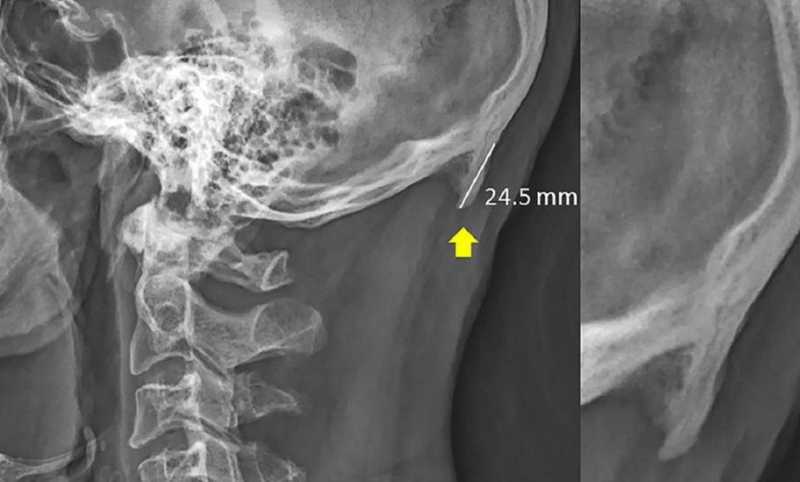

Are Horns Growing On Youngsters Due To Excess Cellphone Usage?

Phone addiction has been a subject of debate for a long time now. The kids of the 21st century have often been accused of unproductively keeping their eyes glued to their phone screens for hours during the day. And honestly, why wouldn’t one be dependent on his/her mobile? After all, phones are becoming increasingly advanced, …